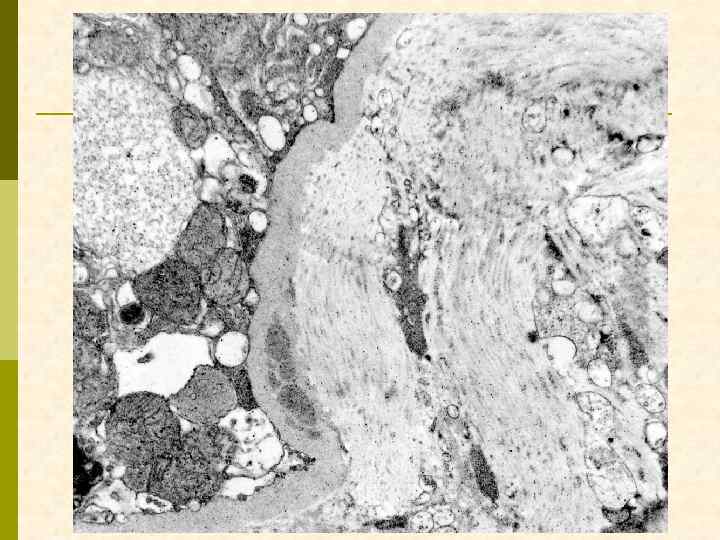

ВИЧ-ассоциированная нефропатия. Тубулоретикулярные структуры в эндотелиоците.

Заключение по ЭМ p В нефробиоптате один частично склерозированный клубочек со значительно утолщенной капсулой, в которой имеются массивные отложения электронно-плотных депозитов и скопления коллагеновых волокон. В неизмененных зонах клубочка гломерулярная базальная мембрана (ГБМ) капилляров неравномерно утолщена с интрамембранной локализацией электронноплотных депозитов. Субэпителиальных и субэндотелиальных депозитов мало. Более массивные депозиты расположены в умеренно расширенном мезангиальном матриксе. В ГБМ коллабированных капилляров обнаружены депозиты смешанного характера с микролипидными включениями. Цитоплазма подоцитов с умеренным набуханием при незначительной микроворсинчатой трансформацией и со слияние малых ножек. HIV-ассоциированные тубулоретикулярные включения обнаружены в цитоплазме многих эндотелиальных клеток гломерулярных капилляров.

депозиты в мезангии и в ГБМ, тубуло-ретикулярные структуры в эндотелиоците

тубуло-ретикулярные структуры в эндотелиоците